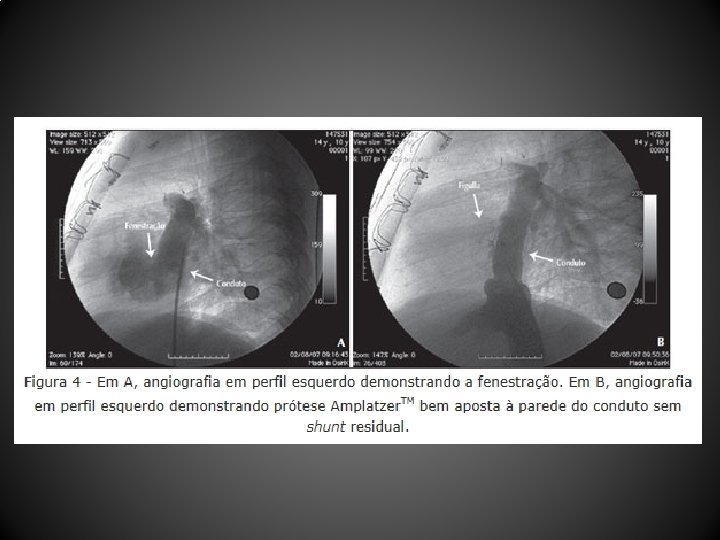

Resultados • Entre abril de 2004 e dezembro de 2010, 12 pacientes (média de idade, 103, 1 + 88, 6 meses; peso, 29, 9 + 12, 7 kg) submetidos a CF (10 tubos extracardíacos, 2 túneis intra-atriais) foram tratados 44, 1 + 26, 7 meses após a CF • Um paciente não tolerou o teste de oclusão com o balão, sendo contraindicado o procedimento • As próteses utilizadas foram: Helex. TM (4 pacientes), Amplatzer. TM (2 pacientes), Cardia Atriasept. TM (2 pacientes), Figulla. TM (1 paciente), Cera. TM (1 paciente), e 1 stent coberto Cheatham-Platinum. TM • Após a oclusão da fenestração, a saturação de oxigênio aumentou significativamente (82, 1 + 6, 5% para 95, 2 + 3, 2%), sem aumento significativo da pressão venosa central (12, 4 + 2, 6 mm. Hg para 14, 5 + 2, 3 mm. Hg) nem queda do débito cardíaco • Após o procedimento foi observado shunt residual imediato em 5 pacientes, que desapareceu antes da alta